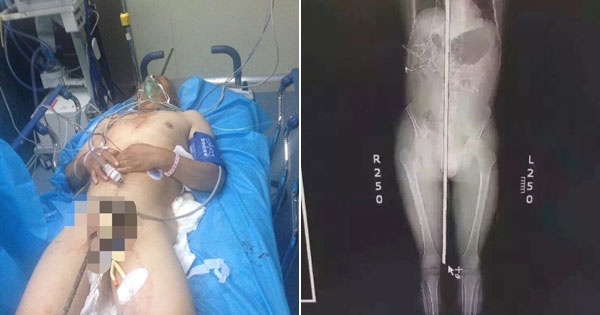

真的触目惊心!

只有在电影里才会出现的满清十大酷刑光是想像就令人头皮发麻,但前几天在中国山东济南发生的一场工伤事件意外把这可怕画面搬到现实中。不慎失足坠落的工人被一…